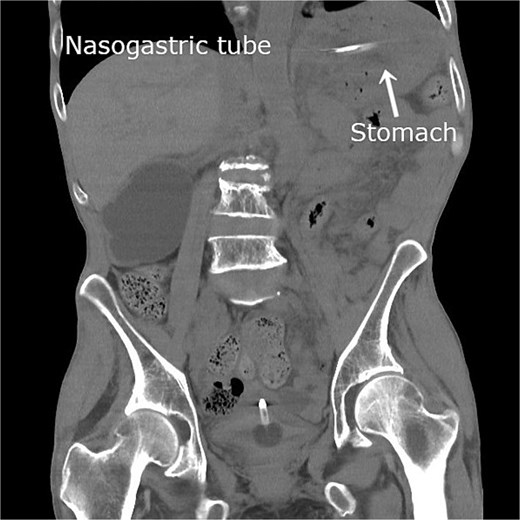

The patient was admitted with an initial diagnosis of gastric incarceration due to internal hernia associated with colostomy (IHAC), complicated by aspiration pneumonia. A nasogastric tube was inserted for decompression using intermittent −30 cm H₂O suction, and intravenous sulbactam/ampicillin therapy was initiated. On the same day following gastric decompression, abdominal symptoms resolved. On the day following admission, follow-up CT confirmed gastric distension resolution and spontaneous hernia reduction (Fig. 2). On hospital Day 6, intravenous antibiotics were discontinued following clinical improvement.

Follow-up plain CT obtained on the day after admission revealing gastric dilatation resolution following nasogastric decompression. The stomach has returned to its normal anatomical position, indicating spontaneous hernia reduction.